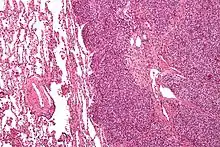

There are typically many small cells of the same size and appearance, with round nuclei.[3] Around half have extensive glycogen deposits, demonstrated with positive PAS staining.[3] Around 85% of Ewing sarcomas are positive for CD99, a cell-surface glycoprotein.[1] However, CD99 also occurs in some normal tissue and in other round cell sarcomas, as well as in lymphoblastic lymphoma and leukemia.[3] There may be keratin expression.[1]

Micrograph of a metastatic Ewing sarcoma with the characteristic cytoplasmic clearing on H&E staining, which was showing to be PAS positive